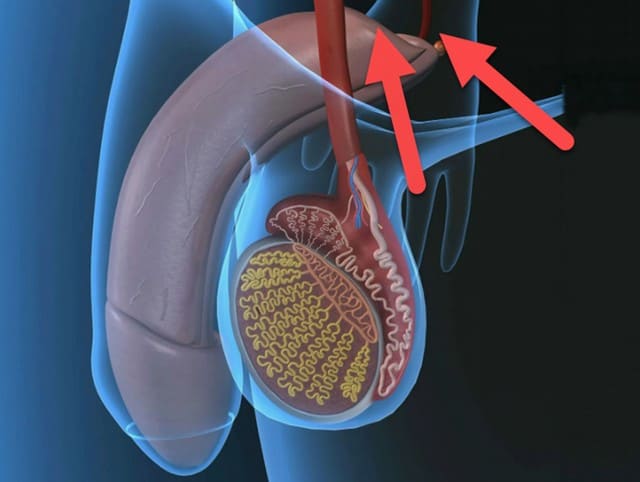

El hecho es que la glándula prostática tiene un flujo sanguíneo complejo. Y precisamente por su desgaste la glándula se debilita, sus propiedades inmunitarias disminuyen y en ella se instalan bacterias patógenas. Eso significa que se desarrolla prostatitis bacteriana.

Talorix Bold restaura el flujo sanguíneo normal en la glándula, después de lo cual se fortalece. Y solo entonces la glándula misma se encarga de las bacterias. Lo que lleva primero a la eliminación de la prostatitis, y luego de la disfunción eréctil (se restaura la potencia como en la juventud).

La glándula prostática tiene un flujo sanguíneo complejo.